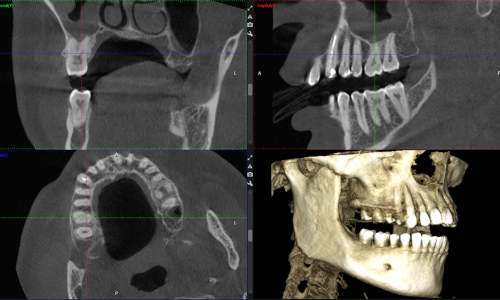

L’imaging dentale viene ottenuto utilizzando l’innovativo TC Cone Beam Planmeca Viso G5, per l’altissima qualità delle immagini e per il comfort e la sicurezza del paziente. Possiamo acquisire una panoramica 2D delle arcate dentali e anche delle immagini 3D straordinariamente realistiche, effettuando immagini paragonabili ad una Tac tradizionale, ma con dose radiogena molto inferiore grazie al sistema Ultra low dose.

Questa apparecchiatura innovativa è utilizzabile per tutti i tipi di indicazioni, ad esempio per valutare la vicinanza dei denti del giudizio ai nervi alveolari inferiori, la quantità ossea per il posizionamento di impianto, i disturbi dell’articolazione temporo-mandibolare, la patologia ossea nelle mascelle, le lesioni traumatiche al viso e le deformità dentofacciali.

La nuova modalità di acquisizione immagini endodontiche 3D per le unità Planmeca Viso permette l’acquisizione di immagini CBCT nitide e uniformi, ideali per l’endodonzia.

Con il paziente si possono condividere le immagini 3D acquisite digitalmente, con la possibilità di vedere le articolazioni, le vie aeree e la posizione dei denti, dal singolo dente al telecranio.